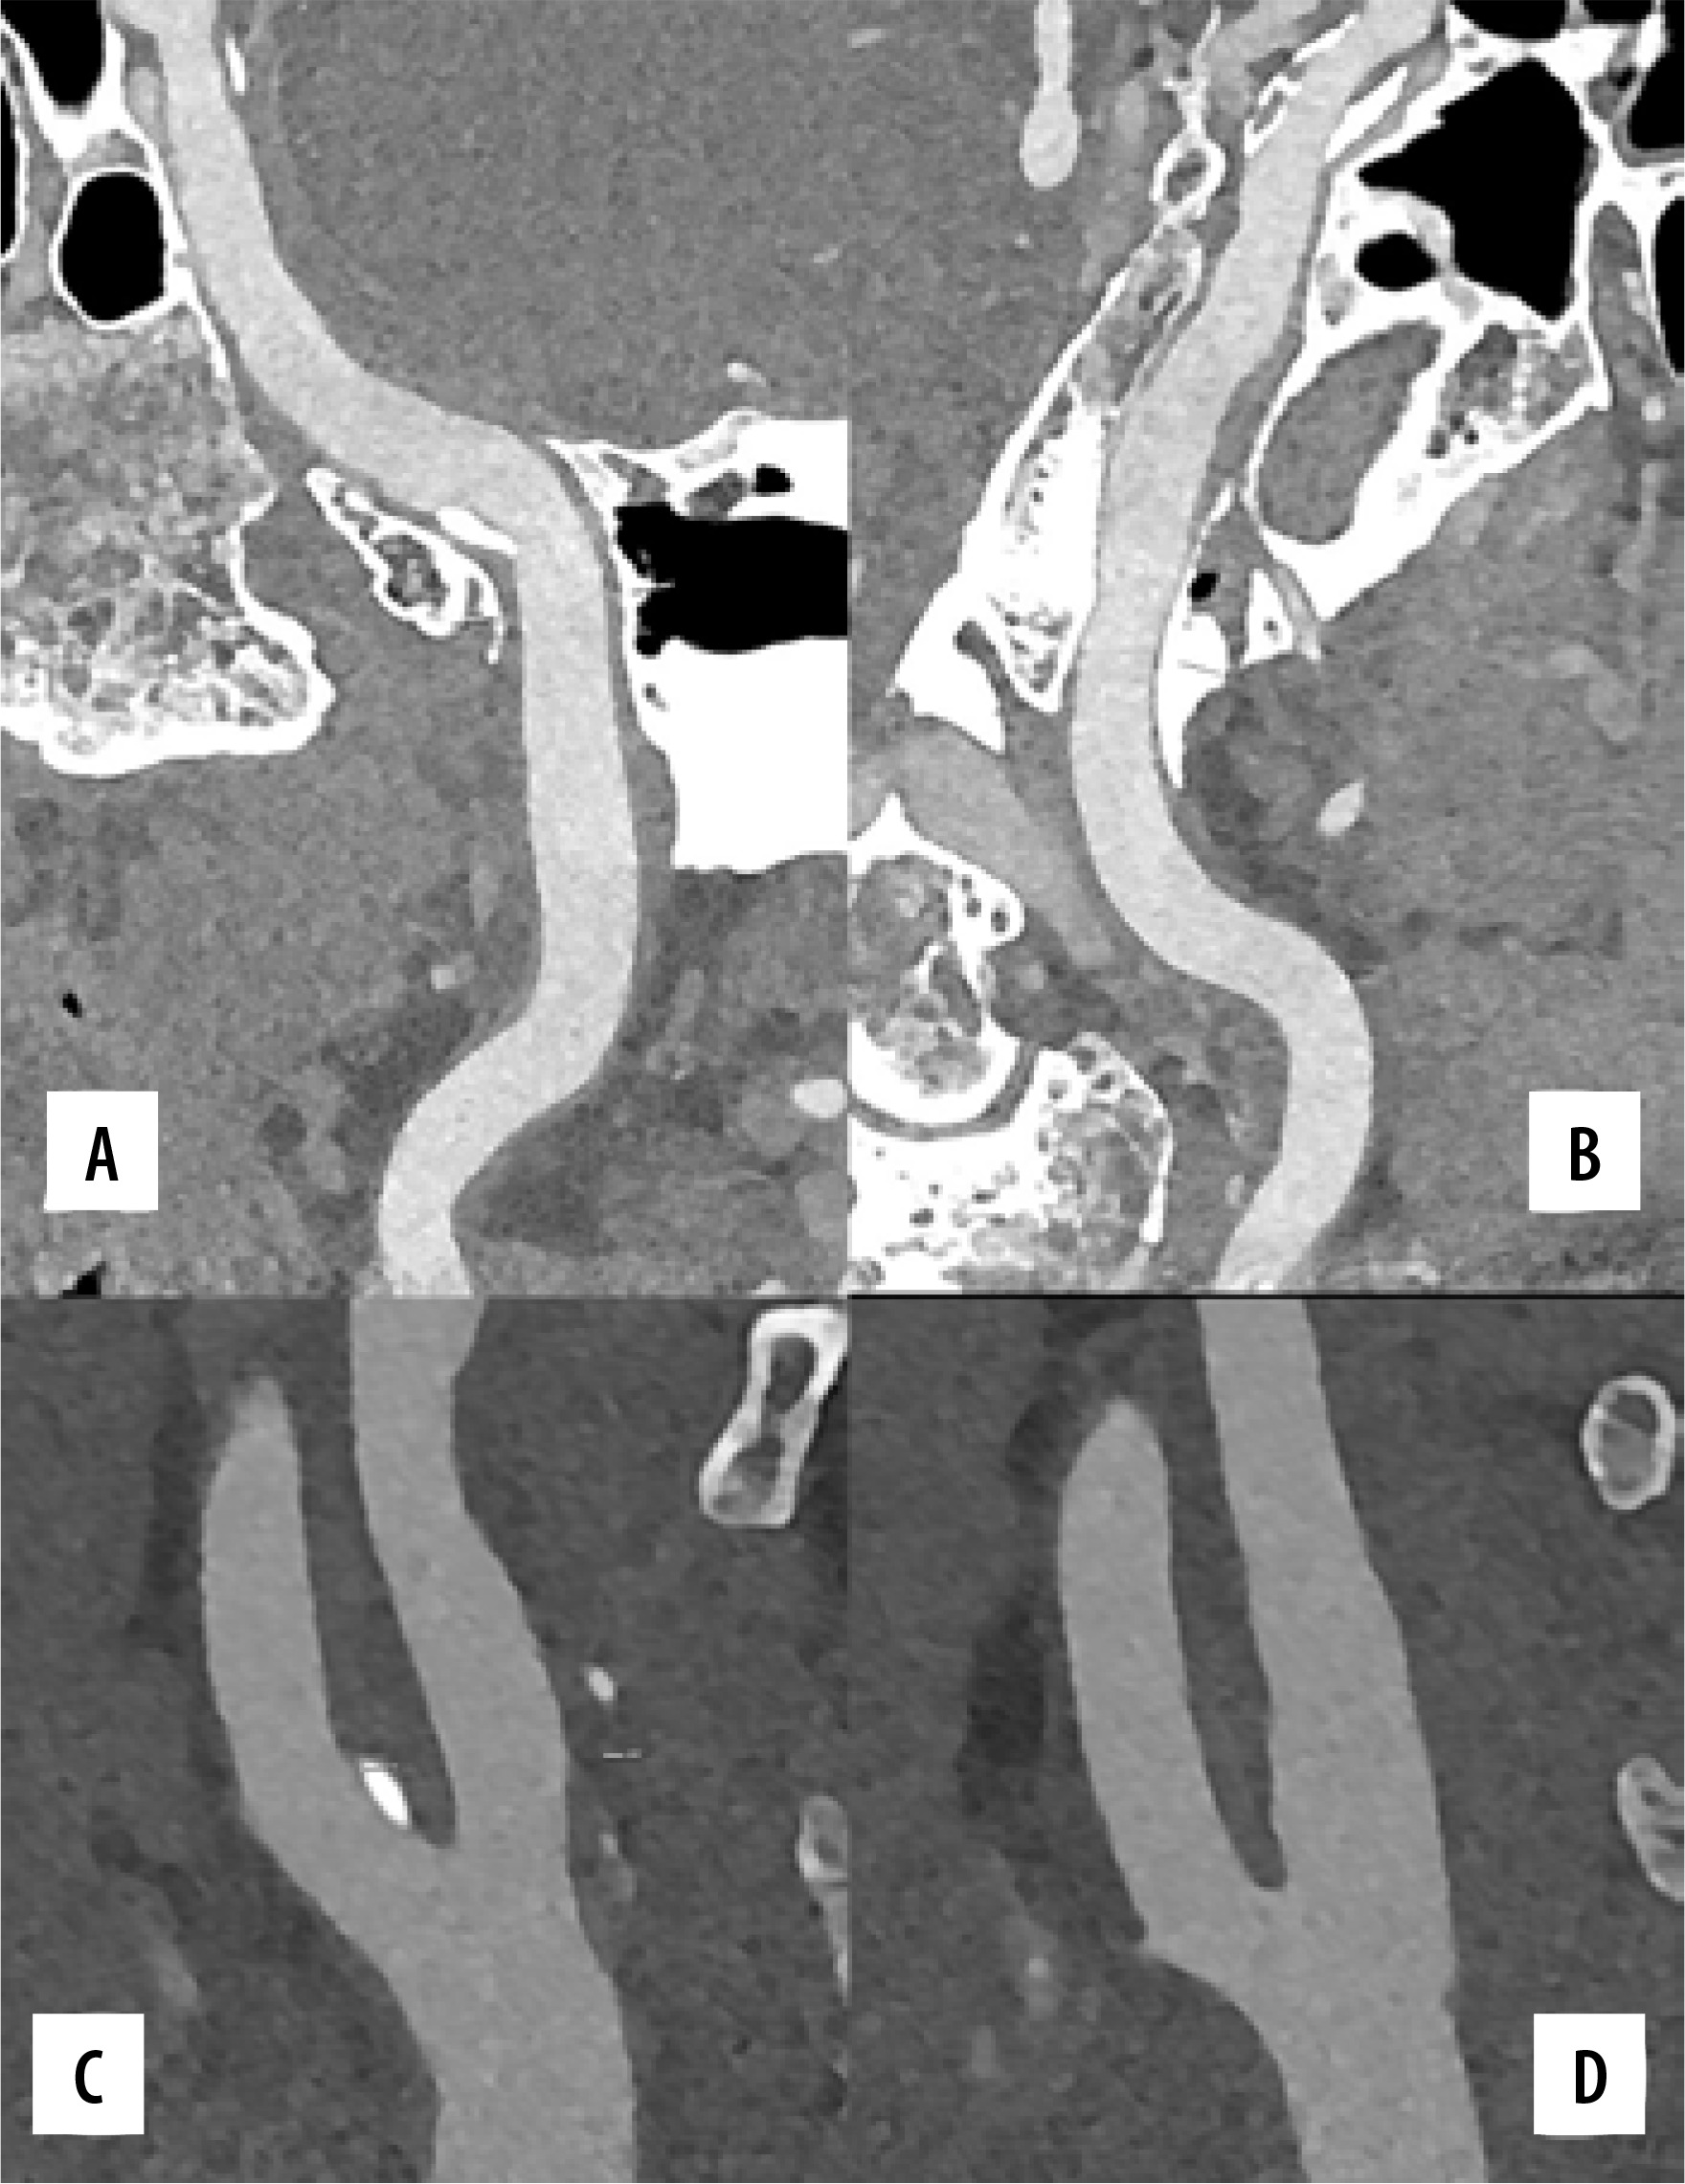

CT angiography (CTA) has replaced digital subtraction angiography (DSA) for first-line vascular imaging in routine clinical practice [30]. Fast 3D isotropic data with high-resolution acquisition is important in CTA [15,30]. PCD-CT will be useful for imaging vessels and the detection of thrombosis with optimal doses (Figures 1 and 2) [15]. Lower extremity ischaemia and below-knee artery calcification cannot be optimally evaluated using conventional CT scans due to insufficient spatial resolution. PCD-CT overcomes these issues thanks to its multi-energetic nature by reducing streak artifacts and improving signal uniformity [31,32].

Figure 1

Photon-counting computed tomography (PCCT) angiography example of the intra-cranial arteries and carotid arteries with mild atherosclerosis. The figure shows the intrapetrous internal carotid arteries (A, B) with a curved multiplanar reconstruction along the central lumen line; the bilateral bifurcation of the carotid arteries is displayed in C (right) and D (left). The scan was performed on a commercial whole-body dual-source photoncounting CT scanner (Naeotom Alpha, Siemens Healthineers, Forchheim, Germany) with 0.2 mm slice thickness, 0.1 mm reconstruction increment, and FOV 140 mm. The images are displayed with a resolution matrix of 1024 × 1024 pixels on the source axial reconstructions with a kernel filtering of Bv60 (vascular kernel medium-sharp) and with the maximum intensity of Quantum Iterative Reconstruction (QIR 4). The actual displayed resolution is 0.1 mm (100 microns)